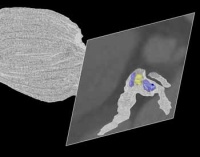

- Segmentation and tree extraction of coronary arteries in MSCT datasets by Victoria Quirante Ruiz

- Boundary extraction of coronary arteries by Alessandro Rigazzi